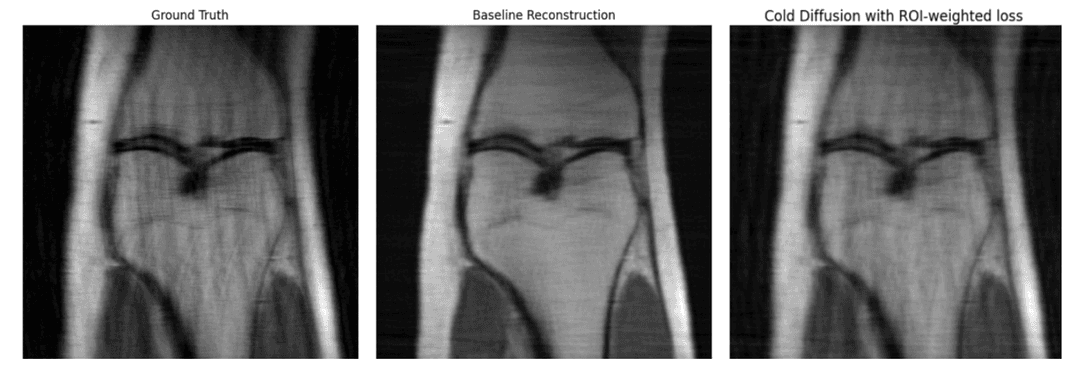

The foundational success set the stage for the main goal: applying the same logic to a state-of-the-art Cold Diffusion model. By enhancing this powerful algorithm with the ROI-weighted technique, we achieved high-impact results, demonstrating a significant boost in image quality across all key metrics.

The ROI-weighted model (right) reconstructs the image with visibly higher detail and accuracy, outperforming the baseline model (center) and closely matching the original ground truth (left).